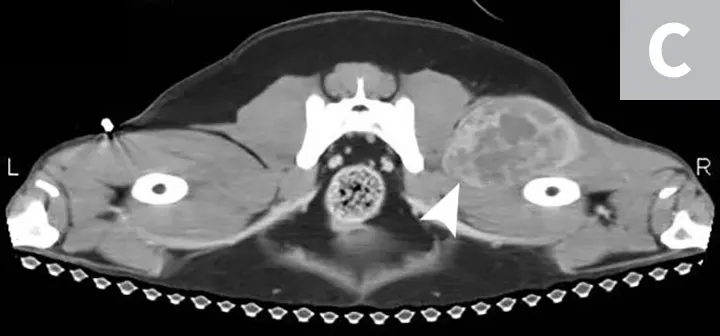

Primary noncutaneous HSA involving the head of the spleen (A) and the right auricle (B, arrowheads). Images courtesy of Laura Garrett, DVM, DACVIM (Oncology), and Louis-Philippe de Lorimier, DVM, DACVIM (Oncology)